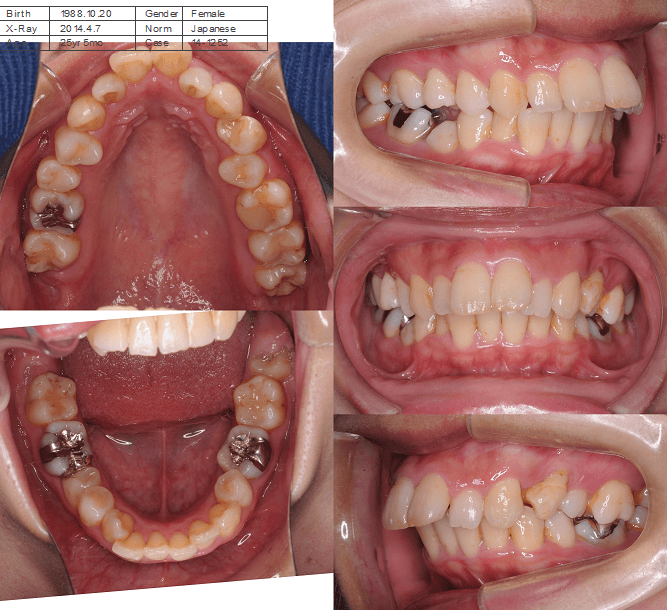

| 年齢・性別 | 25歳女性 |

|---|---|

| 主訴 | 前歯の歯並びの乱れ(叢生)を気にされて来院された25歳女性。咬み合わせや審美的な改善を希望されていました。 |

| 治療期間・回数 | 4年5ヶ月・30回 |

| 費用 | 1100,000円(税別) |